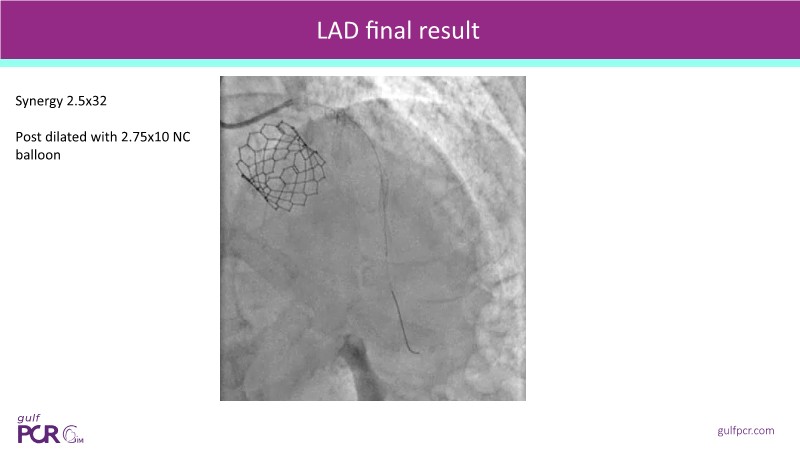

Calcified coronary lesions are a major challenge in PCI. This PCRGulf-GIM 2025 session showcases a complex case with intravascular imaging, highlighting how IVUS 123 guides each step.

From planning the procedure and understanding calcium distribution, to lesion preparation with modern modification tools, and post-PCI assessment to confirm stent expansion and detect complications, this session demonstrates practical, imaging-driven strategies.

Learn how careful preparation and modern techniques improve outcomes in treating severe calcium, calcified nodules, and in-stent restenosis.